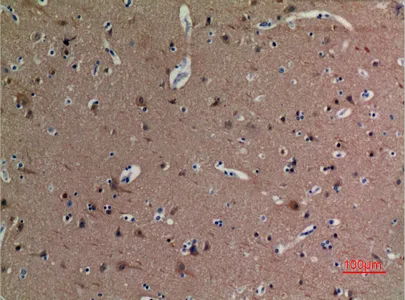

YAP (phospho Ser127) Rabbit Polyclonal Antibody

Cat: APRab05637